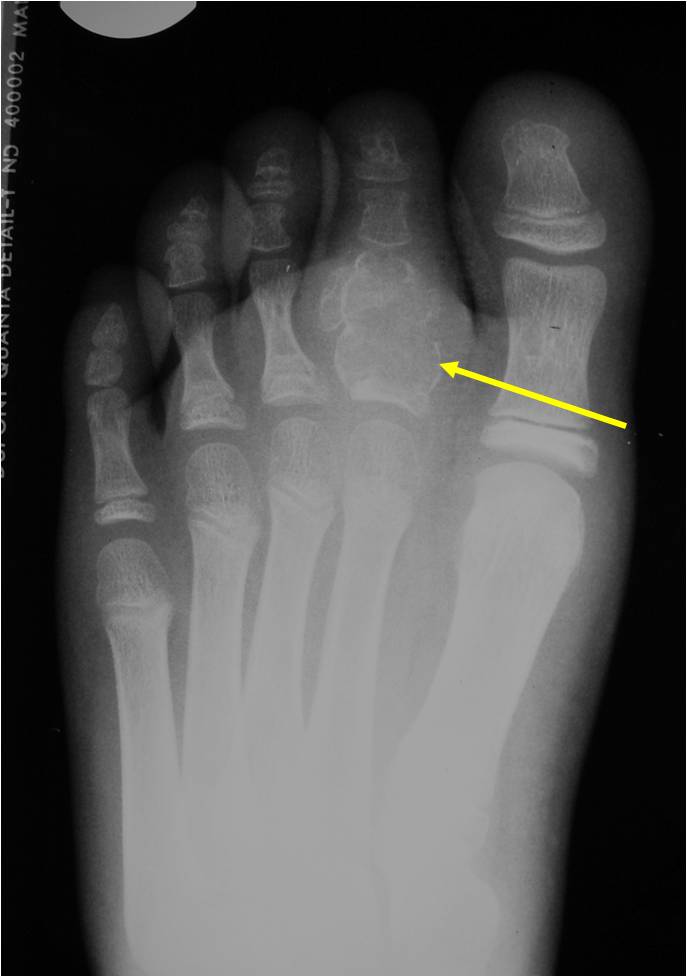

Radiographic Presentation

- Presents as a highly defined/well circumscribed geographic oval/round lytic defect

- Surrounded by rim of sclerotic bone

- Usually in epiphyseal region

- Lesion ranges from 3 cm to 6 cm diameter

- Usually radiolucent

- May have fine trabeculae and irregular calcifications

- Calcifications are often better detected with a CT scan but are not uniformly present

- Lesions may expand the bone and new periosteal bone may form

- Bony end plate, cortex, bone contour are unaffected

- (Plain x-ray appearance)

- Geographic lytic lesion IA/IB margin of sclerosis

- Usually Eccentric more often than Central in the bone

- Rarely expansile (rarely penetrates the cortex)

- Calcified chondroid matrix 30%-50% of cases

- Often better detected with a CT Scan

- Periosteal Reaction 30-50% of cases

- Usually occurs in Adjacent Diaphysis/Metaphysis since epiphysis is intraarticular and not surrounded by periosteum